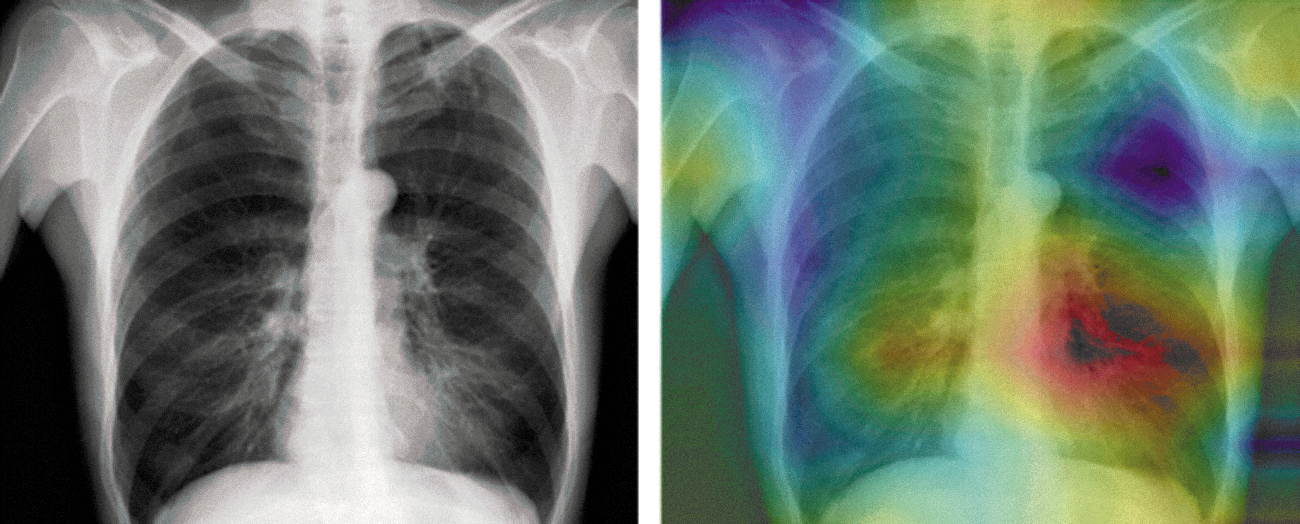

Since that time, research and applications with DNNs have exploded with new challenge problems and applications. Over the last five years, neural models have been used in multiple applications, including scene recognition systems used in semiautonomous driving. In another domain, DNNs have been demonstrated to perform at expert levels with interpreting medical imagery. For example, DNNs have been shown to have the capability to provide expert-level classifications, such as the diagnosis of dermatological disorders from images of skin28 and diagnoses from radiological films (Figure 8.1).29

Figure 8.1. Visualization generated by CheXNet model, highlighting a region in a radiological image of the thorax, where the system recognizes right pleural diffusion. Pranav Rajpurkar et al., “CheXNet: Radiologist-Level Pneumonia Detection on Chest X-Rays with Deep Learning” arXiv, December 25, 2017, https://doi.org/10.48550/arXiv.1711.05225.